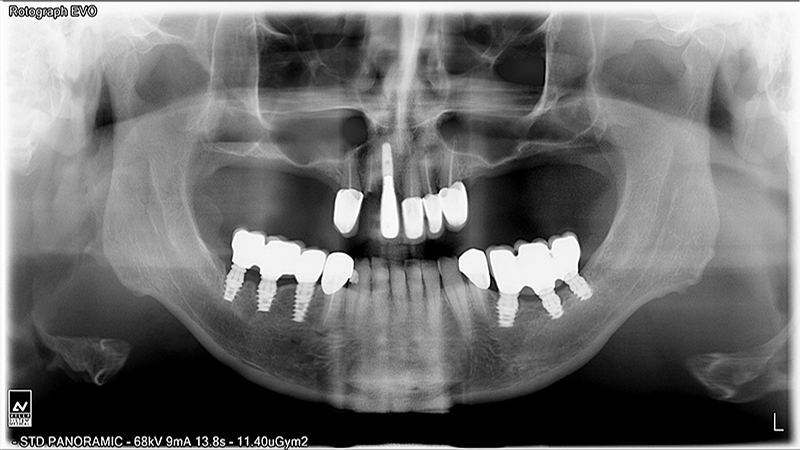

Implants

Implant Patients